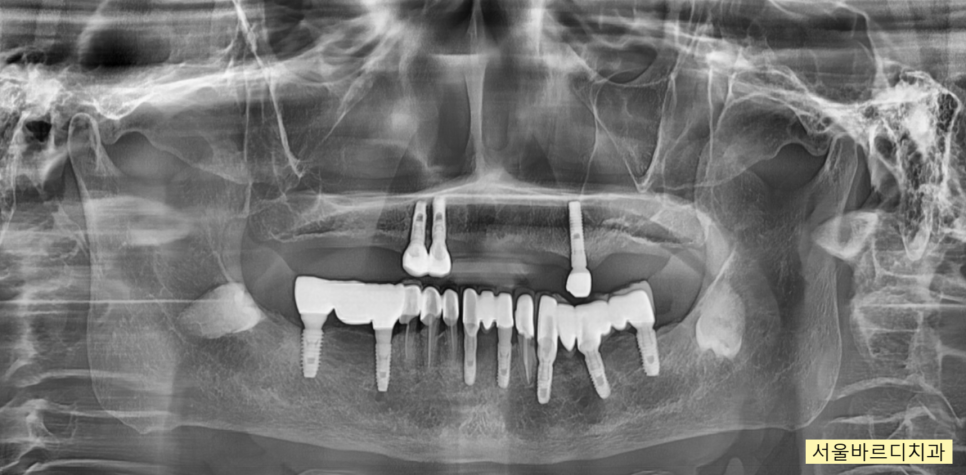

241031 치료계획입니다~~ 기존 심겨진 임플란트를 활용하면서 회복해주는 계획이죠.

이미 기존에 임플란트가 심겨진 것이 3개가 있고

아래 치아도 대부분 임플란트이기에

부분 틀니에서 임플란트 바꿔서 치료계획을 세워드렸는데요.

241129

임플란트는 연령에 상관없는

뼈만 있으면 할 수 있다는 것을

ct를 통하여 보여드리고

환자분이 가지고 있는 두가지 문제

위, 아래 치아와의 궁합 관계를 고려하여

임플란트가 적절함을 설명드렸죠.

치료 과정에서

기존에 심겨진 임플란트는 최대한 활용하였습니다.

임플란트는 뼈 안에 식립되어있고

높이를 올리는 것은 보철을 통해 해결해주기 때문에

문제가 되지 않습니다.